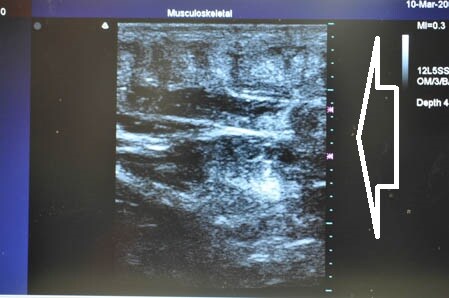

右の腰も見ておきましょう。

↓ ↓ ↓